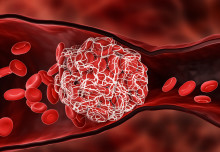

Blood clot-busting nanocapsules could reduce existing treatment’s side effects

Enzyme’s ‘molecular scissors’ cut out fatal blood clot risk when injury strikes